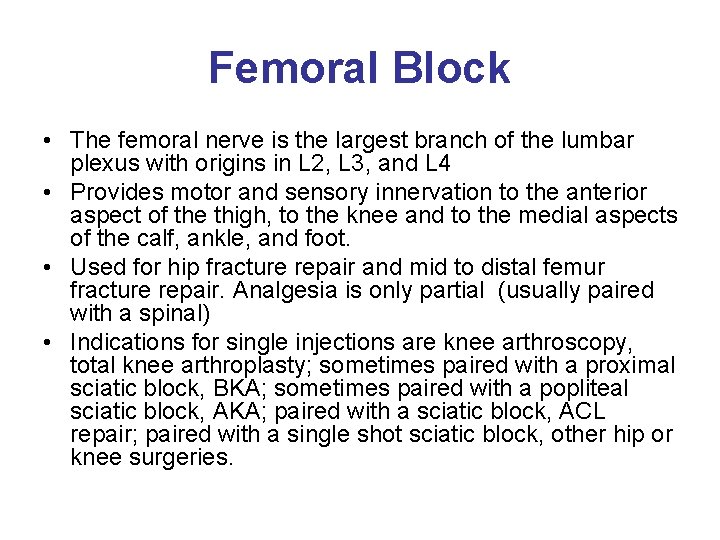

Femoral Block • The femoral nerve is the largest branch of the lumbar plexus with origins in L 2, L 3, and L 4 • Provides motor and sensory innervation to the anterior aspect of the thigh, to the knee and to the medial aspects of the calf, ankle, and foot. • Used for hip fracture repair and mid to distal femur fracture repair. Analgesia is only partial (usually paired with a spinal) • Indications for single injections are knee arthroscopy, total knee arthroplasty; sometimes paired with a proximal sciatic block, BKA; sometimes paired with a popliteal sciatic block, AKA; paired with a sciatic block, ACL repair; paired with a single shot sciatic block, other hip or knee surgeries.